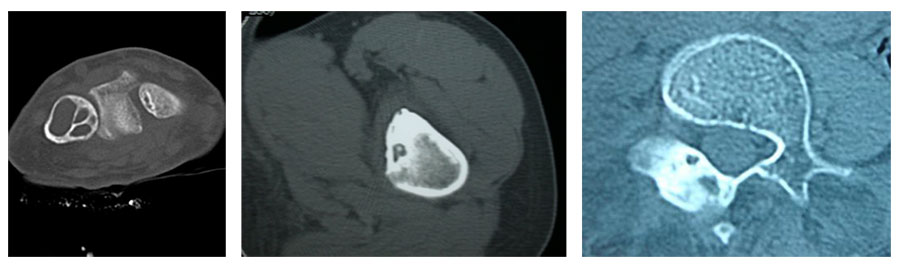

Bone tumors are rare lesions. A large part of these tumors are benign lesions, and they often occur by chance during radiological examinations for another reason. As a complaint, they usually show swelling and pain. Rarely, it is diagnosed after causing a fracture in the place where it was. Osteoid osteoma, osteochondroma (exostosis), enchondroma, non-ossifying fibroma, eosinophilic granuloma, simple bone cyst, fibrous dysplasia and intraosseous lipoma/ganglion are the most common lesions of benign tumors.